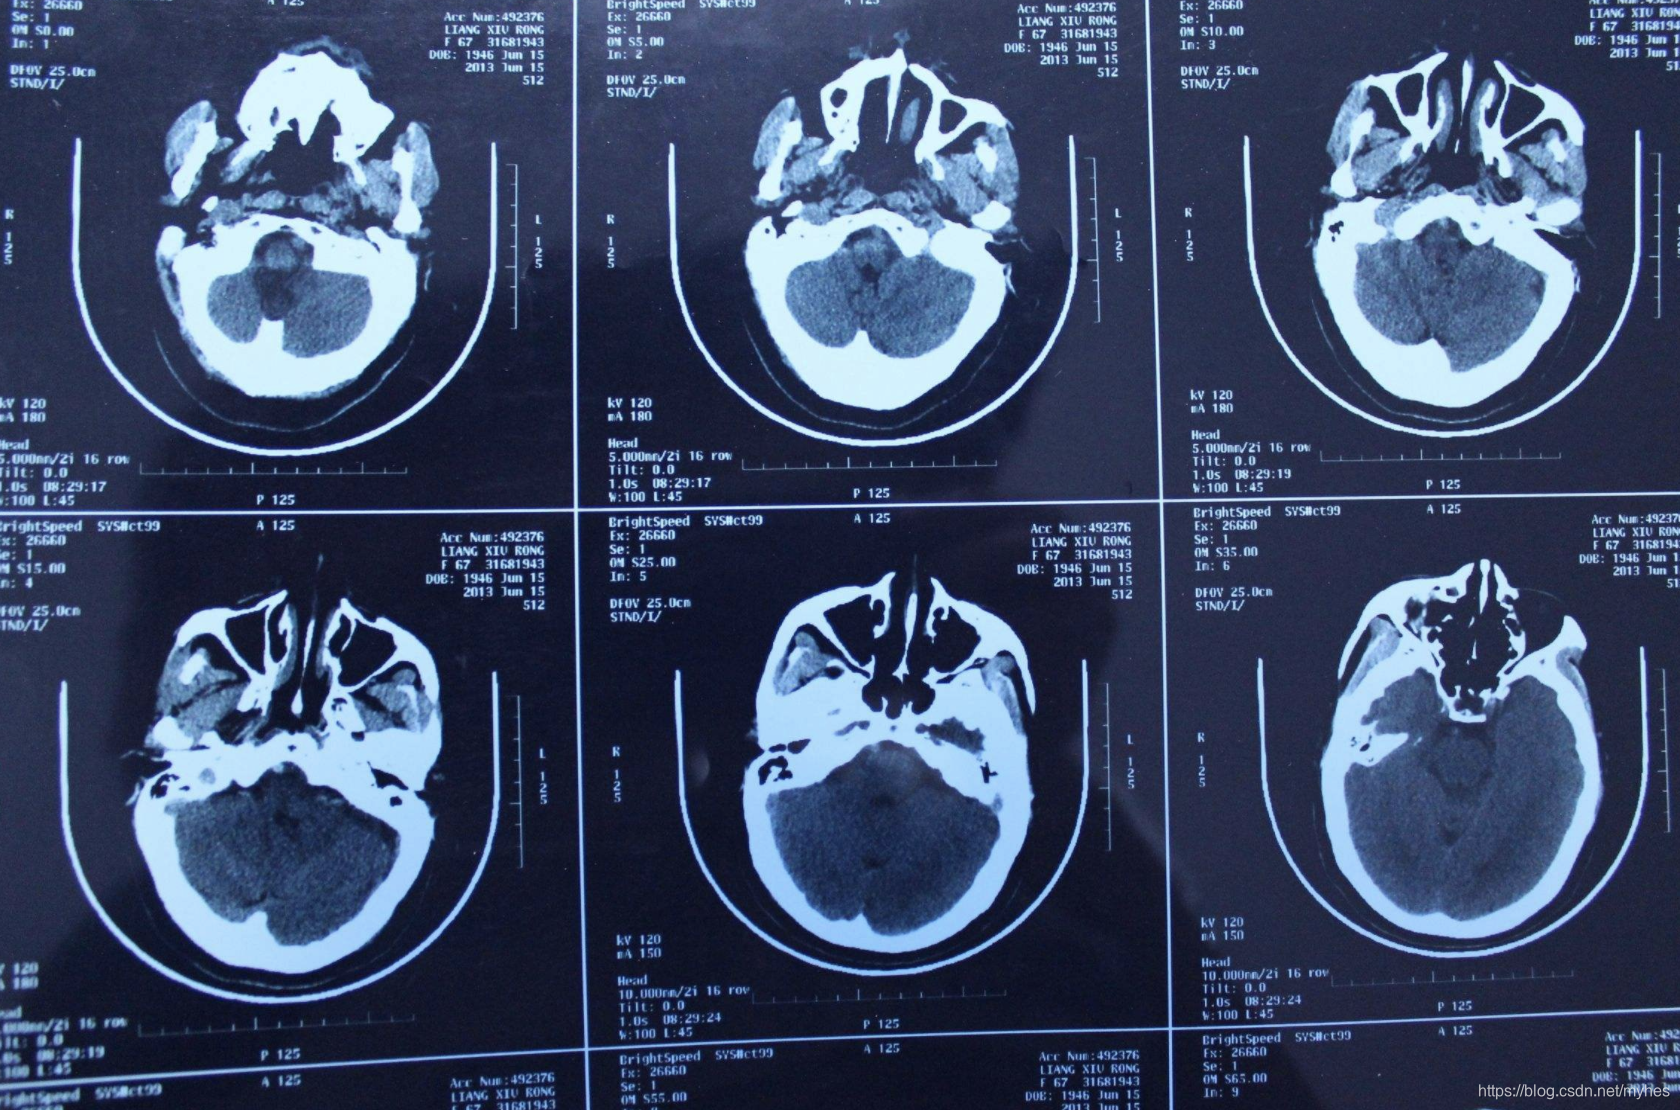

CT扫描 (Computed Tomography,CT)

CT也称 CT扫描,是外科室的主要探查手段之一,对于层级较多的组织,采用CT较为合适,比如颈部、胸部、骨骼、肿瘤等通常会采用CT扫描。

CT意为X线计算机断层摄影,是用X线束对人体某部进行断层扫描,获得人体被检部的断面或立体图像。CT可以提供人体被检查部位的完整三维信息,可使器官和结构清楚显影,清楚地显示病变。就像把一片面包切成片来看。

CT成像原理

CT是用X射线束对人体某部一定厚度的层面进行扫描,由探测器接收透过该层面

的X射线,转变为可见光后,由光电转换变为电信号,再经模拟/数字转换器(analog/digital converter)转为数字,输入计算机处理。

图像形成的处理有如对选定层面分成若干个体积相同的长方体,称之为体素(voxel)。

扫描所得信息经计算而获得每个体素的X射线衰减系数或吸收系数,再排列成矩阵,即数字矩阵(digital matrix),数字矩阵可存贮于磁盘或光盘中。经数字/模拟转换器(digital/analog converter)把数字矩阵中的每个数字转为由黑到白不等灰度的小方块,即像素(pixel),并按矩阵排列,即构成CT图像。所以,CT图像是重建图像。每个体素的X射线吸收系数可以通过不同的数学方法算出。

CT的工作程序是这样的:它根据人体不同组织对X线的吸收与透过率的不同,应用灵敏度极高的仪器对人体进行测量,然后将测量所获取的数据输入电子计算机,电子计算机对数据进行处理后,就可摄下人体被检查部位的断面或立体的图像,发现体内任何部位的细小病变。